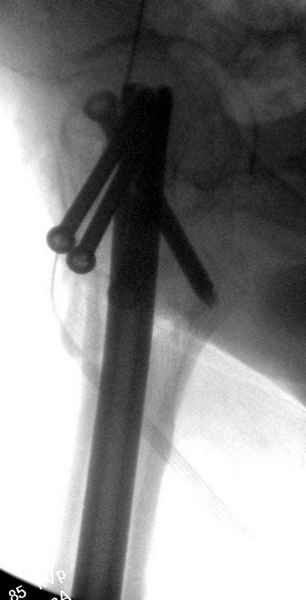

Правильно, ситуация изменилась, как говорят у нас теперь "different animal", надо решать проблему подвертельного перелома. При наличии различных вариантов фиксаторов, включая Страйкер Гамма 3, мы выбрали DePuy Antegrade Trachanteric Nail из-за многовариантности проксимальной фиксации и двойного изгиба. Вводится через вертел под 8 градусным углом, и есть достаточный передний диафизарный изгиб, предупреждающий пенетрацию дистального переднего кортекса.

Кто знает что дальше, мысленно готовы к проксимальной артропластике.